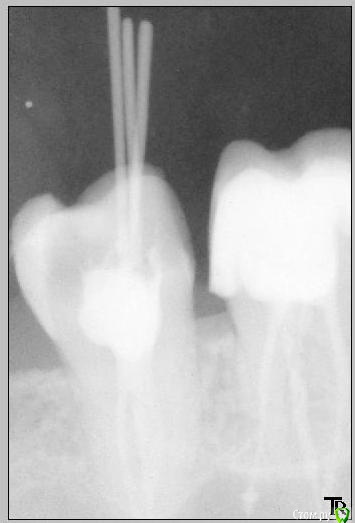

Katya88 Опубликовано 22 декабря, 2014 Поделиться Опубликовано 22 декабря, 2014 Всем здравствуйте. Ситуация такова: заболел зуб справа наверху, болевые ощущения на холодное и горячее, боль при накусывании, к ночи боль усиливалась. У стоматолога сделали снимок, под вопросом были 26 и 27 зуб, снимок этих зубов до лечения №1. В 26 зубе была полость, врач сказал что начнет сверлить, если камера пульповая не вскроется, то удалять ничего не надо, собственно она осталась целой. стоматолога и в 27 кариес, в общем на первом приеме запломбировали оба, стоматолог сказал что если будет ныть то значит в 26 пульпит. Боли не прекратились, а усилились и через неделю мне депульпировали 26 зуб. Сильные боли прекратились, но полностью не исчезли. Через 10 дней боль опять усилилась, и снова появлялась на холодное и горячее, при накусывании и усиливалась к вечеру. Я пошла к стоматологу, путем прикладывания ватки смоченной в горячей воде выяснилось, что болит 27 зуб! И удалили в нем нерв, боли прекратились. Вопросы: мне ошибочно удалили нерв в 26 зубе? Виноват стоматолог? Если пульповая камера целая, то пульпита быть не должно? Как качество запломбированных каналов? Читала что хороший врач на обработку одного канала тратит не менее 30 мин, мой стоматолог три канала обрабатывает за 20 мин))) Мне нужно менять врача? Могло ли быть следующее, сначала пульпит в 26 зубе, а потом в 27? Ссылка на комментарий

CRAZYDUCK Опубликовано 23 декабря, 2014 Поделиться Опубликовано 23 декабря, 2014 Вот такие снимки делают в частных стоматологиях, это оригиналы, не сканы и не перфотографированныену контрастность на компе врач регулирует и все хорошо видно, а эти снимки скопировали Вам сильно засвеченными почему-то.Пульпит мог быть и в двух сразу зубах, могло так совпасть конечно же. Сделайте еще снимки , потому , что по таким невозможно ничего понять.Пульпит может быть , к сожалению, и в невскрытой полости. Ссылка на комментарий

Shaid Опубликовано 26 декабря, 2014 Поделиться Опубликовано 26 декабря, 2014 Это может быть либо другой зуб, либо дополнительный(не найденный) канал у леченного зуба. Ссылка на комментарий